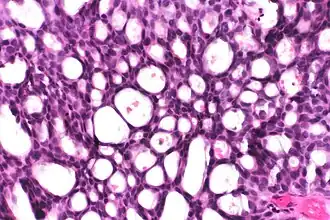

Cribriform: Solid with multiple clear spaces. -